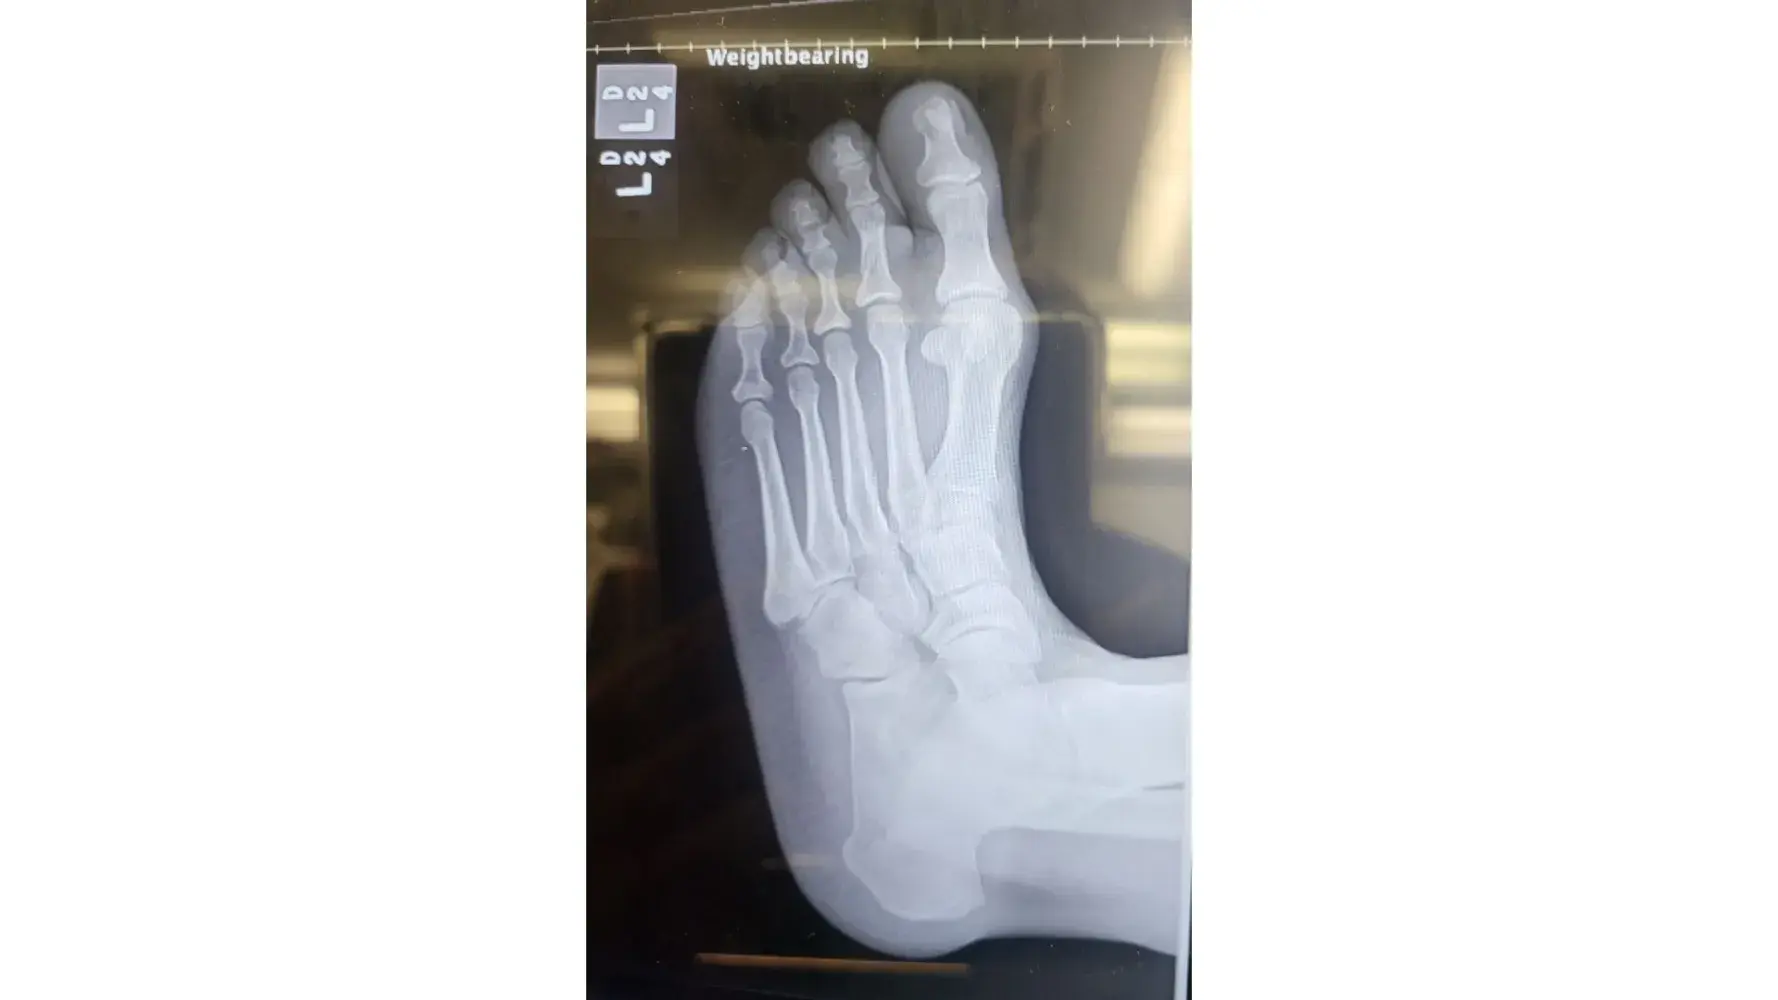

I checked in the resort on December 1, 2022. I prepaid for a Marvelous suite Months ago to celebrate my Birthday in Panama City. When I entered the room #1923. I went to sleep after a long day of travel. As the daylight began to come through the patio door I got up to close the curtains. Without realizing the sofa bed (let out murphy bed) between the King bed and patio door was broken and protruding out at the bottom. This area should've been flush to the sofa. My foot hit the edge of this and caused severe pain. I laid back down until morning break. I called down to the hotel lobby from the room to report what happened. I was instructed someone would be coming up to take a look. No one ever showed up. Later in the day (Dec. 2nd) after elevating my leg in the room I came down to speak with someone at the desk. A report was made in the resort computer By Domingo. I also spoke with David about the matter. Maintenance was asked to go to the room to fix the sofa and ice was sent up. It was a failed attempt, the piece still protruded away from the sofa. I asked for a Manager, I was told he would not be in until the next morning. In the meantime An EMT from the resort was asked to come look at the foot. She did a quick look and concluded it was NOT fractured but bruised. Her Recommendation was to ice and elevate the foot and to stay off of it. She said it will hurt and stay swollen for a few days. This was not my idea for a vacation. The next morning (Dec. 3rd) I stopped at the desk limping. My entire foot was swollen and throbbing. I spoke to David again and showed him my swollen foot from the injury. I waited for the Manager to become available. He spoke with me and apologized for the inconvenience. He offered to move me to another room which I did to avoid any further injuries. On Dec 4th I checked out. I When I arrived home I still had pain and trouble walking but expected to get better according to the Resorts EMT. On December 14th, 2022 I went to the Friends Family Health Clinic because there was no relief. The Nurse indicated that the swelling would have gone down before now if it was only bruised and ordered an Xray. I went directly to the University Of Chicago Hospital for the Xray. I received a call shortly after arriving back home from the Doctor, he confirmed that the left foot 2nd toe is fractured. (broken). This has caused me PAIN & SUFFERING. It has been difficult to function daily duties at home or work.

Desired outcome: Refund for entire stay at the RIU and reimbursement for prepaid activities that I could not enjoy. Doctor visits. Pain & Suffering. Total $5,000.00Monica J Allen708-945-9925

Update by Monica J Allen

Dec 15, 2022 12:19 pm UTC

photos from Xray